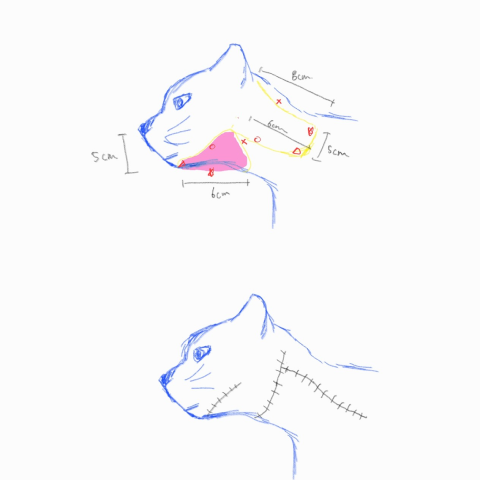

심한 염증으로 발생한 아래턱 피부 결손

수술 전 플래닝

성형 수술 후